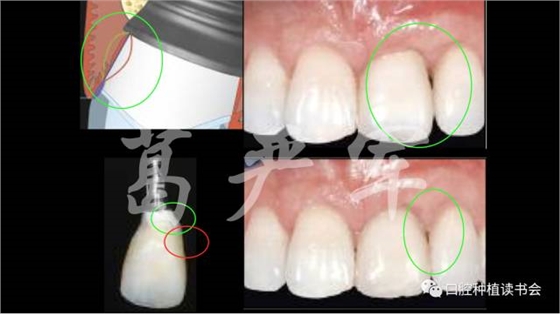

病例一,右上1缺失,在種植臨時修復(fù)期間,通過臨時冠的塑形,在正式修復(fù)后達到了比較令人滿意的治療效果。

病例二,右上12缺失,在長達半年的種植臨時修復(fù)期間,五次調(diào)整臨時修復(fù)體的穿齦外形,但幾乎沒有對粘膜邊緣的位置及右上1、2之間齦乳頭高度產(chǎn)生任何影響,正式修復(fù)后的美學(xué)效果也很差。